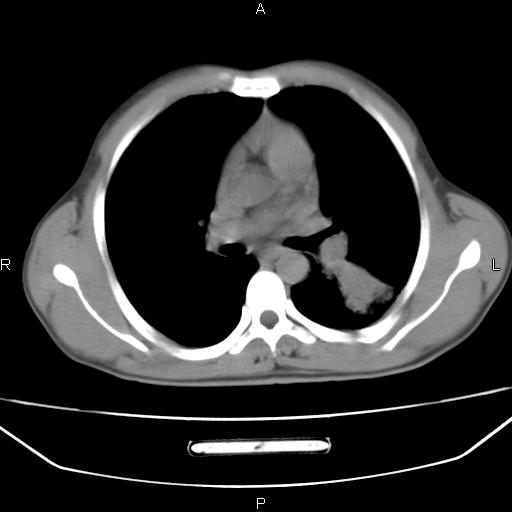

患者,男,40岁。间断发热,咳嗽二十余日。体温最高达38.9° 在当地诊所抗炎治疗三天后体温降至正常,患者自行停药。今又发热。胸片示,左下肺阴影。

左下肺片状高密度影,境界模糊,密度不均,考虑感染性病变可能性大,建议抗炎治疗后复查。左肺门增大,不除外占位性病变,必要时支气管镜检。